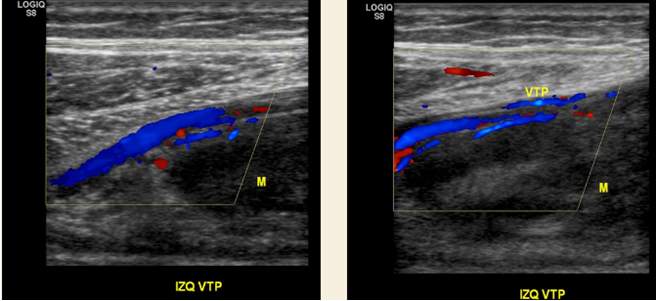

Se realiza protocolo por TVP. Paciente semisentado.

Negativo para trombosis

En relación a aumento de volumen en pierna izq. se observa gran masa sólida, hipoecogénica, heterogénea y escasamente vascularizada en plano interfascial profundo al soleo que desplaza plano muscular y vascular en íntima relación al nervio tibial. Impresión a un Schwannoma.

Se evalúa de manera dirigida aumento de volumen a nivel de la pierna observando imagen nodular hipoecogénica, heterogénea de 16 x 3,5x 6,1 cm. Presenta flujo estudio con Doppler.